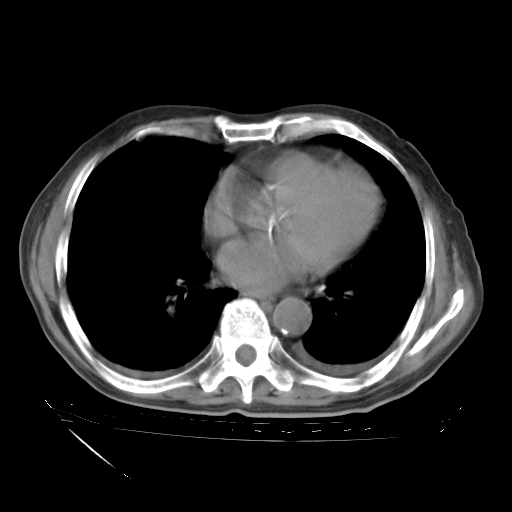

甲强龙80mg/日+抗结核治疗(异烟肼+利福霉素+乙胺丁醇)10天。复查肺部CT。

治疗10天肺部CT